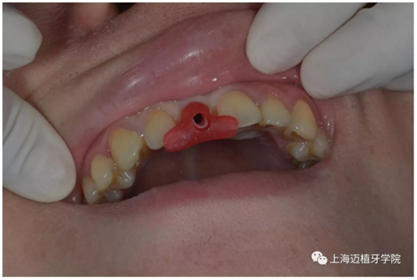

拔除殘根切開(kāi)翻瓣

植入植體DTS:4.1*10 15A042/0061